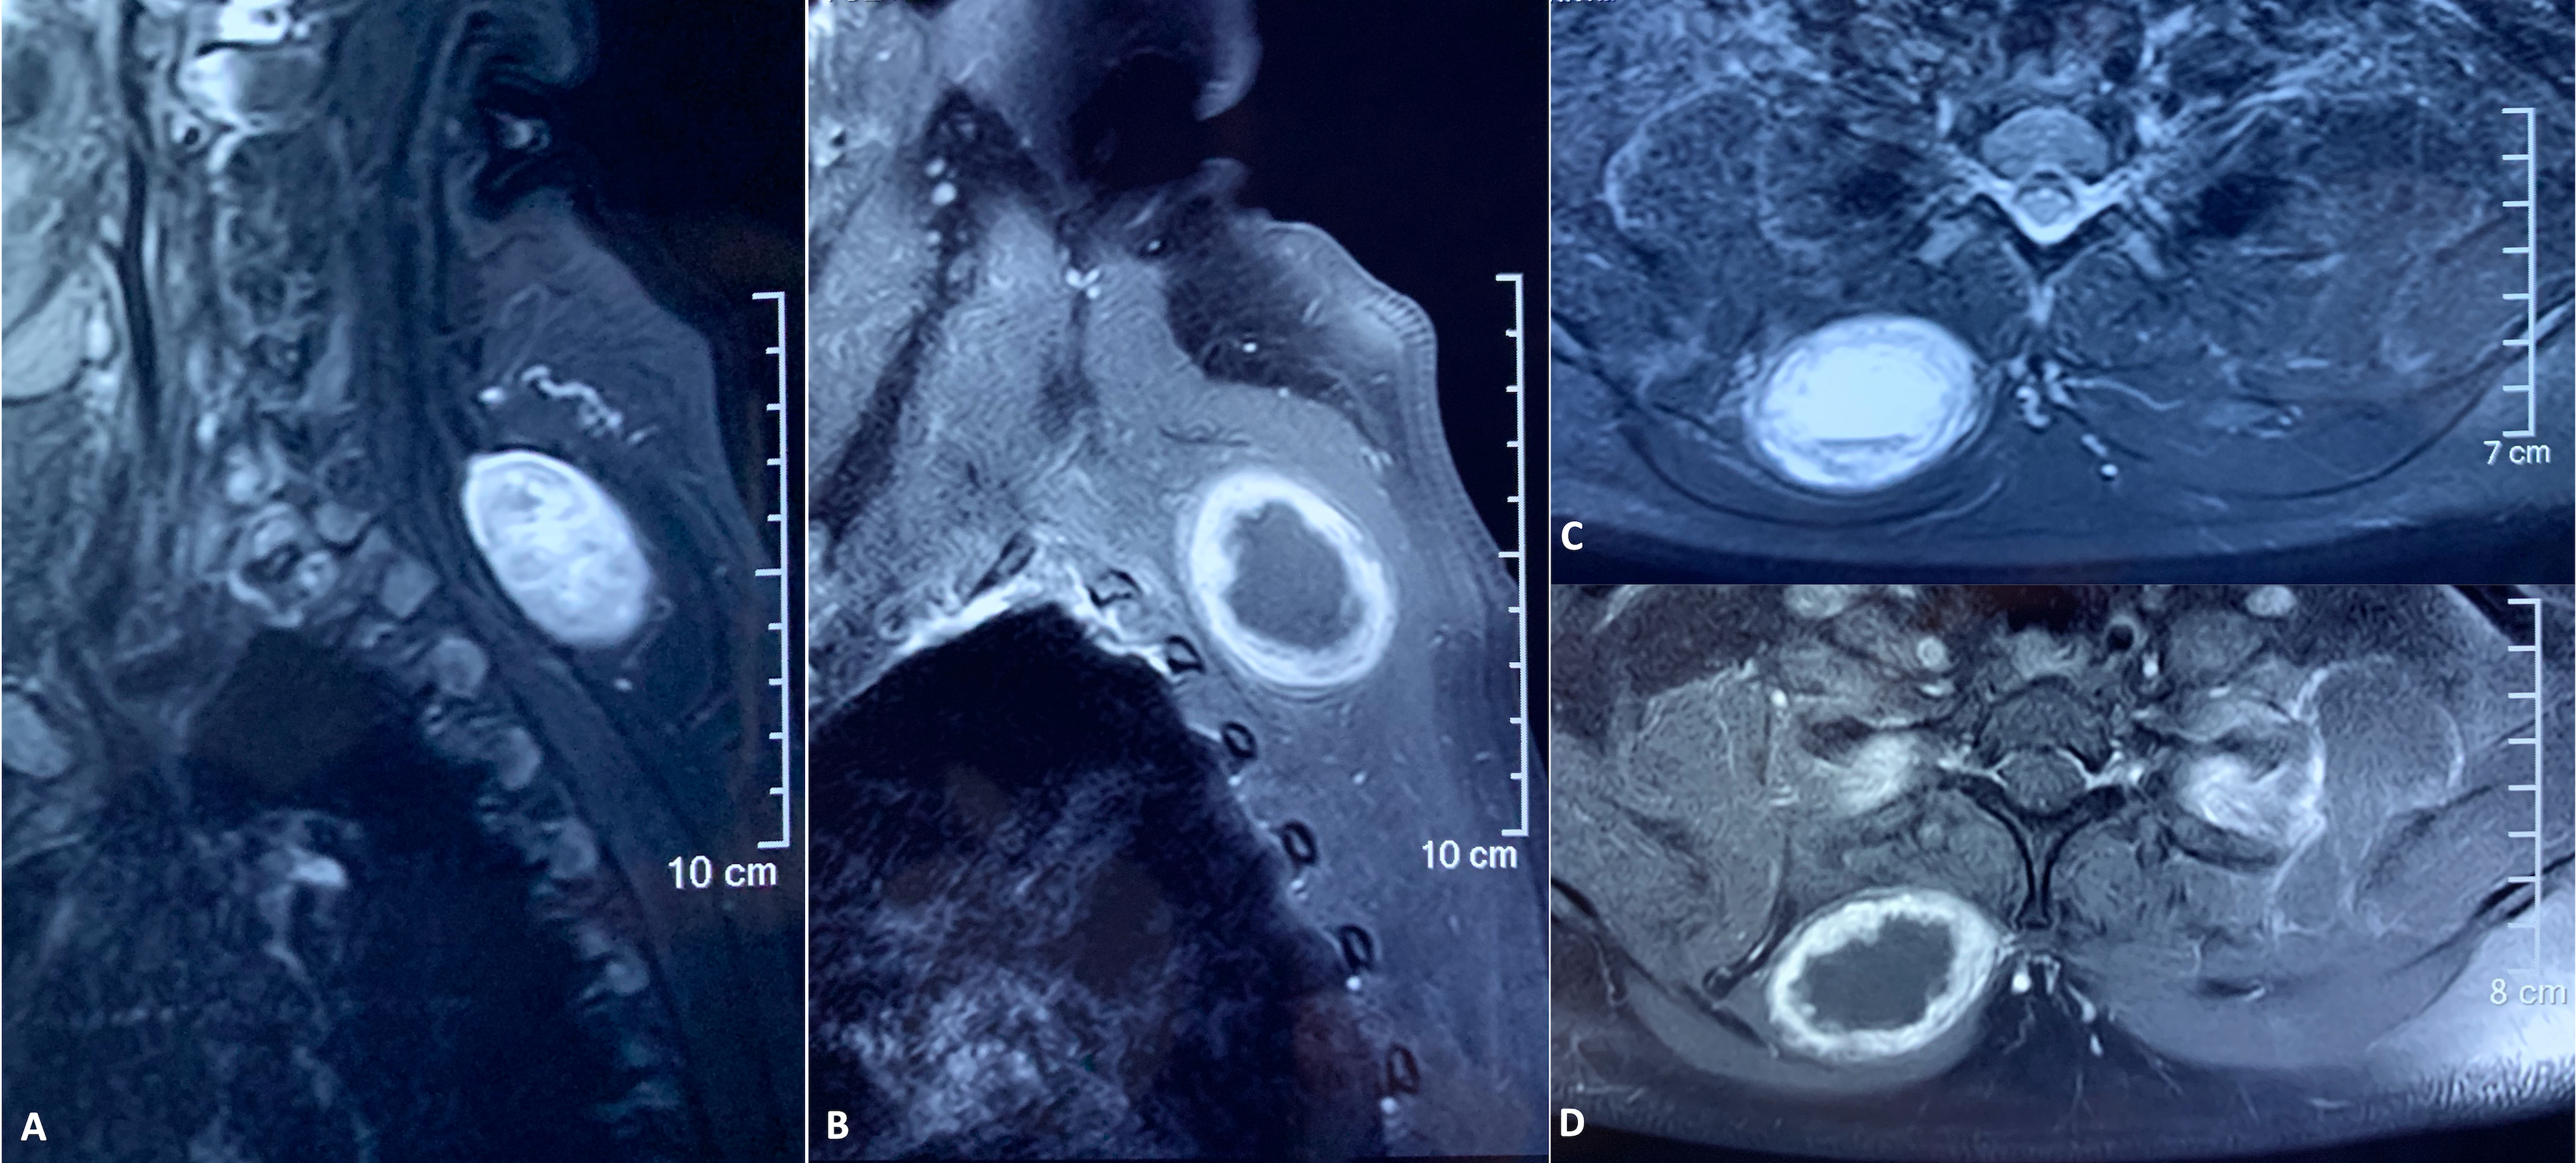

kolkata, West bengal Dec 3, 2021 (Issuewire.com) - Top Indian plastic surgeon, Dr. Srinjoy Saha, is bringing attention to a new case study of a rare spinal tumor that could have gone untreated without early detection. The woman was 44 years old when she had an enlarged but painless swelling on her upper back which turned out to be a schwannoma, which is a type of non-cancerous tumor that grows from cells that cover and protect nerve cells. This kind of schwannoma has hardly been documented before and that calls for greater vigilance in the medical field.

The patient's tumor was not fully diagnosed on the MRI and it did not have any of the characteristics of a schwannoma. With this in mind, Dr. Saha recommends that any slow-growing swelling, including purely cystic tumors, be removed and tested. Surgical removal of the tumor prevents any long-term complications. The findings in his published case report are important and will help ensure that symptoms don't go overlooked, even if they point to a different diagnosis. The scientific paper was published in a significant medical journal on spinal surgery.